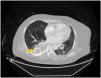

En el control radiológico (fig. 1) y tomografía axial computarizada (TAC) toraco-abdominal (figs. 2 y 3) se identifica un cuerpo extraño compatible con la prótesis, localizado en la cavidad pleural derecha con derrame pleural asociado y atelectasia compresiva sin evidencia de soluciones de continuidad en la pared esofágica. Es valorada por cirugía torácica, procediéndose a la extracción de la prótesis sin incidencias a través de minitoracotomía.